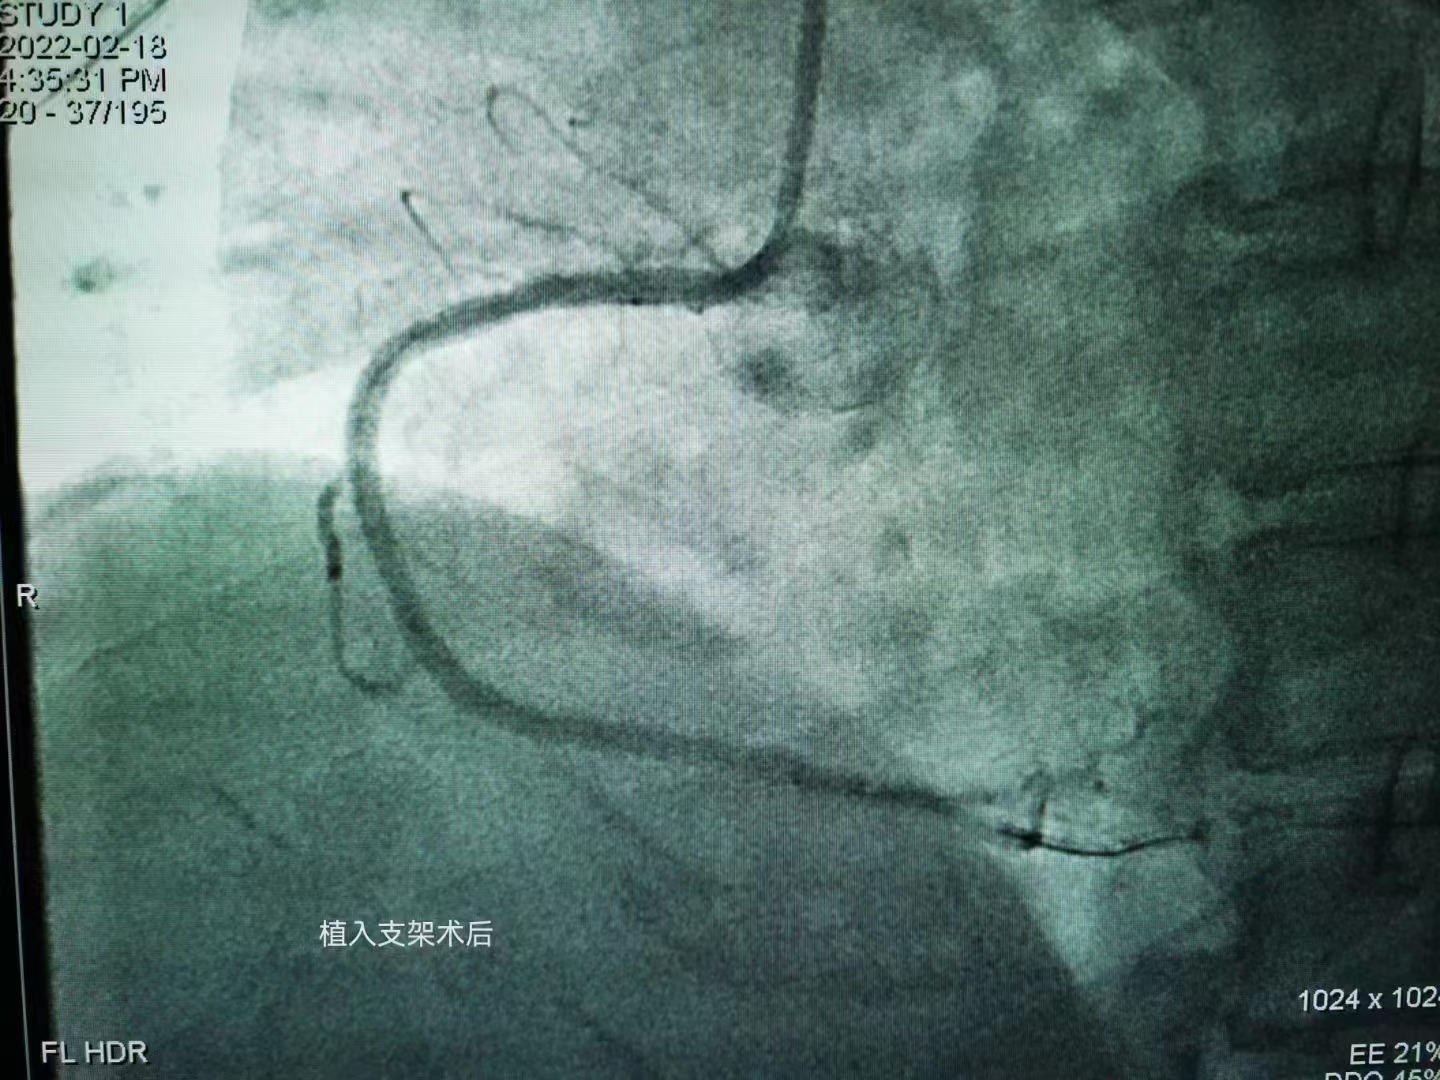

祝賀大連醫科大學附屬第二醫院醫院趙昕專家團隊成功為患者植入Xinsorb生物可吸收支架! 精準操作,完美貼壁

祝賀大連醫科大學附屬第二醫院醫院趙昕專家團隊成功為患者植入Xinsorb生物可吸收支架!

精準操作,完美貼壁